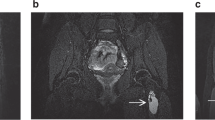

Spondylocostal dysostosis was present in three unrelated girls: a newborn with a severe from, a 16-year-old girl and a 17-month-old infant both with a mild form of the disease. They had clinical and radiographic manifestations typical of the syndrome, and in addition, several abnormalities not described previously. The latter included a right ovarian cyst and hypoplasia of the left leg in Patient 1, and aplasia of the left kidney in Patient 2. The three patients, each with different clinical manifestations, illustrate genetic heterogeneity of the syndrome.